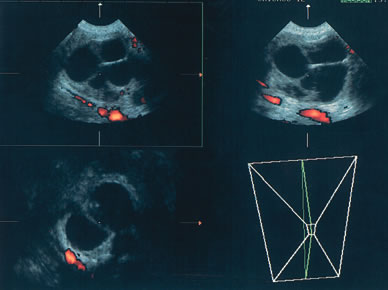

Fig. 1. Three-dimensional orthogonal images of a simple 4-cm cyst in a premenopausal woman. The image in the bottom right is a rendering of a portion of the inner cyst wall. No excrescences were noted. The cyst resolved spontaneously.

Fig. 3. A 3-dimensional study in a perimenopausal patient identified a multiloculated 3.5-cm cyst. Power Doppler examination was unremarkable. Surgery revealed a benign cystadenoma.